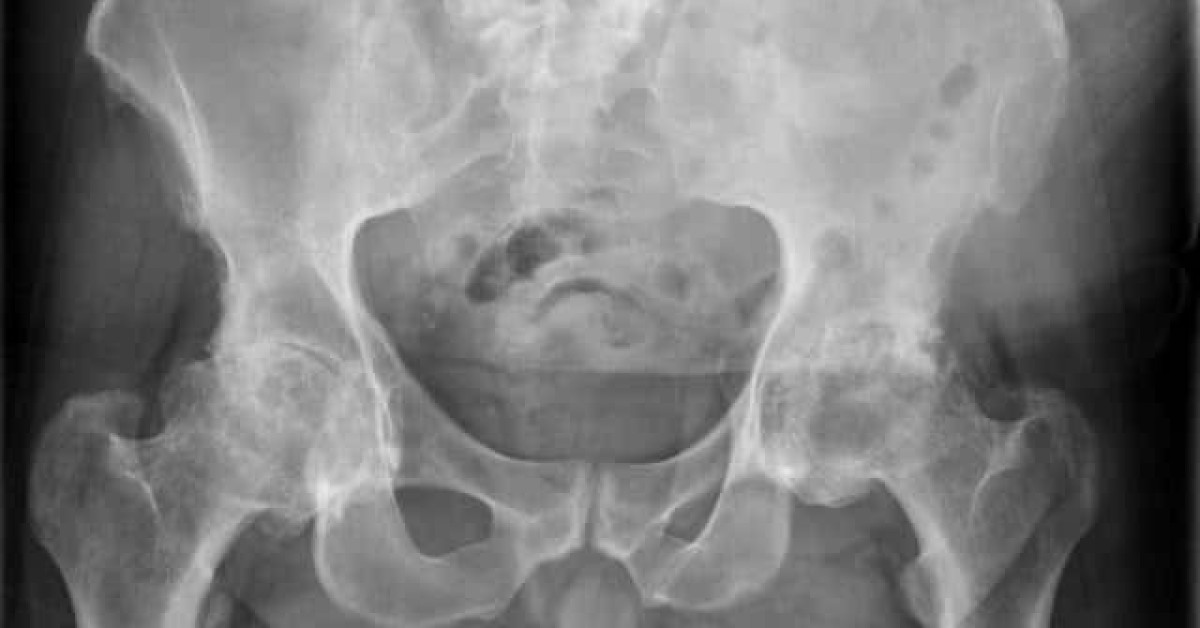

what are primary and secondary match structures on AP imaging?

primary: pubic symphysis or pelvic brim

secondary: obturator foramen or iliac crests

what rotational translation could be suggested with a mismatched obturator foramen?

A roll rotation: one hip is higher than the other

What structures are useful for assessing symmetry during global assessment?

Obturator foramen, pelvic inlet, iliac crests, femoral heads.

What indicates a roll error on a/p imaging

Pelvic inlet or obturator foramen not lining up; one hip higher than the other.